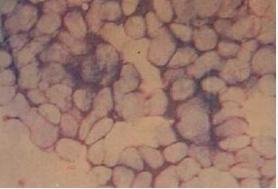

组织病理:病变要在表皮表皮高度增生而伸入真皮,其周围真皮结缔组织受压而成假包膜,并被分为多个状小,真皮乳头受压,而成为小间的异常狭窄的间隔,基底细胞大致正常,自棘层细胞起逐渐变性,在早期,感染细胞始有卵小体成,以后细胞体积逐渐增大,胞核固缩,最后整个胞质均为嗜酸性包涵体(软小体)所占据,在表皮中部,软小体已超过受累细胞原有的体积,细胞核被挤于一侧,固缩成新月,甚至完全消失,在粒层水平处,软小体自嗜酸性变成嗜碱性,角质层可有很多嗜碱性软小体,因并非所有棘细胞都有上述变性,故在细胞中间仍可见少数角化不良的细胞,在病变中央,变性细胞可落而成中央腔隙并与各状小相通,真皮无变化。

潜伏期2~3周,初起为帽针头至绿豆大小的半球状丘疹,表面呈蜡样光泽,中央脐窝状,为正常肤色,渐增大至豌豆大,挤之可排出白色状软小体, 儿童多见于面,躯干四肢(图1),成人全身各处均可发生,由性传播者见于外阴,部,小及大腿侧,也可出现于、颊黏膜、眼结膜等处,数多少不 等,在分布,相互不融,自觉瘙痒, 慢性病程,有自限性,持续数月可自退,多见于儿童及青年人,潜伏期为14天~6个月,初起为米粒大半球丘疹,以后逐渐增至豌豆大,中微凹或呈脐窝,表 面有蜡样光泽,早期质地坚韧,后逐渐变软,呈灰白色珍珠色,可挤出白色样物质,称为软小体,损害数不等,由数个至数十个,陆续出现,或少数 在,或数个簇集,互不融,体表各部位皆可发生,好发于躯干,四肢,肩阴囊和肛门等处,也可发生于,颊黏膜及结膜,皮疹部位因接触式不同而 异,一般无自觉症状,极少数病人其损害异常巨大称为巨型软,有的可角化而像小的皮角,称为角化性软,皮损偶然可自然消失,愈后不留瘢痕。